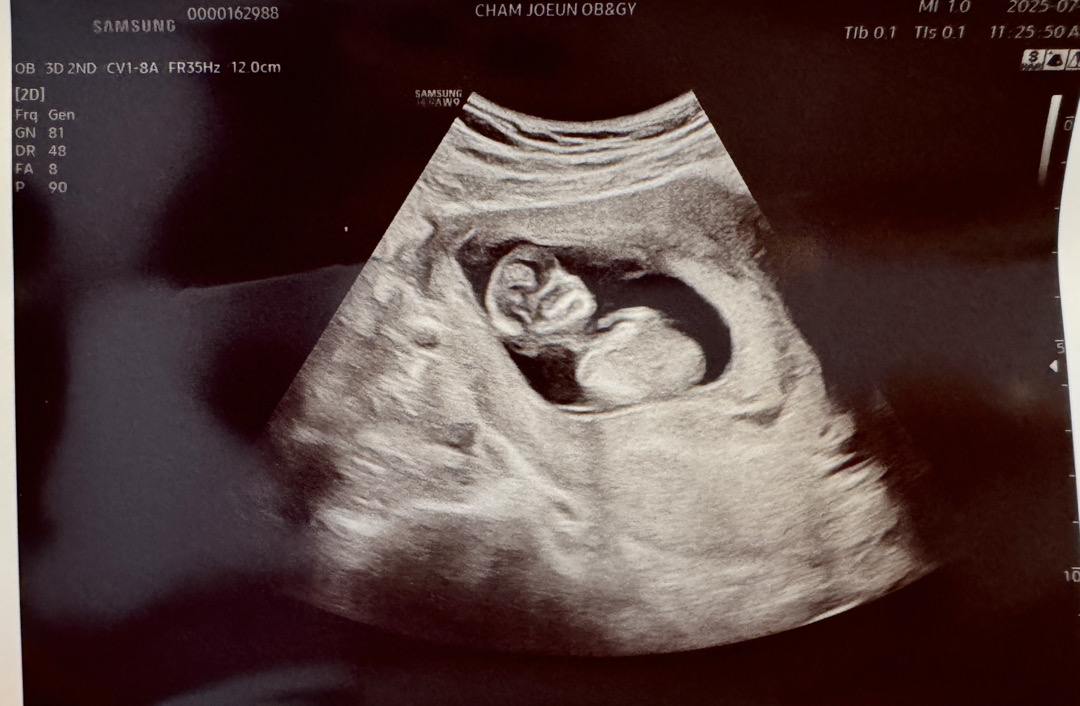

12주 2일이에요-!!

오늘 1차 기형아 검사하고왔어요 한달만에 병원가는거라 은근히 불안하구 그랬는데 다행히 심장도 잘뛰고 목덜미두께도 정상! 그와중에 갑자기 너무 사람(?)모양이라 엄청 신기했어용 ㆅㆅㆅ 양수가 적은편이라 물 많이 마시라구하시구 짠거..매운거… 밀가루.. 금지당햇어요 ㅋㅋㅋㅋ 비빔면… 비빔국수… 참아봐야겠죠…